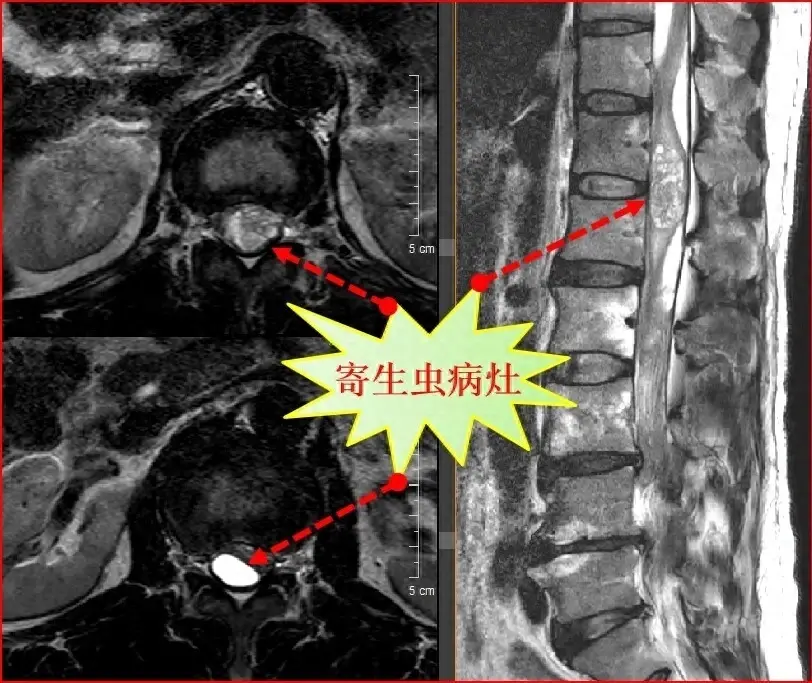

一位男子长期坚持吞食蛇胆并饮用蛇药,近日15年来的习惯竟然引发了罕见的身体异常。这起医学奇闻引起了专家的关注,其病情引发广泛的讨论。

近日,一则医学奇闻引起了人们的注意:一位长期崇尚传统疗法的男子因为15年来持续吞食蛇胆并喝下蛇药,最近竟然发生了罕见的身体异常。这个震撼的故事引起了许多人对于健康的警示和思考。

这位男子,现年45岁,曾经自称是传统医学的拥护者。他长期坚信蛇胆具有神奇的疗效,能够提高免疫力并延缓衰老。因此,他每天都会特意选择吞服一颗新鲜的蛇胆,并将其浸泡在蛇胆草药酒中,坚持了整整15年。

然而,不幸的是,最近他开始出现了一系列病症,包括严重的胃痛、恶心和呕吐,同时他的肌肉也变得僵硬无力。经过多次检查和专家的诊断,惊人的结果让人震惊:这位男子的身体出现了严重的中毒症状,导致其器官功能受损。

专家表示,这起案例再次提醒我们,虽然传统医学有其特殊价值,但绝不能片面迷信,过度的依赖某种疗法会对健康造成不可逆转的损害。蛇胆含有大量的毒素,长期食用必然会对身体带来负面影响。